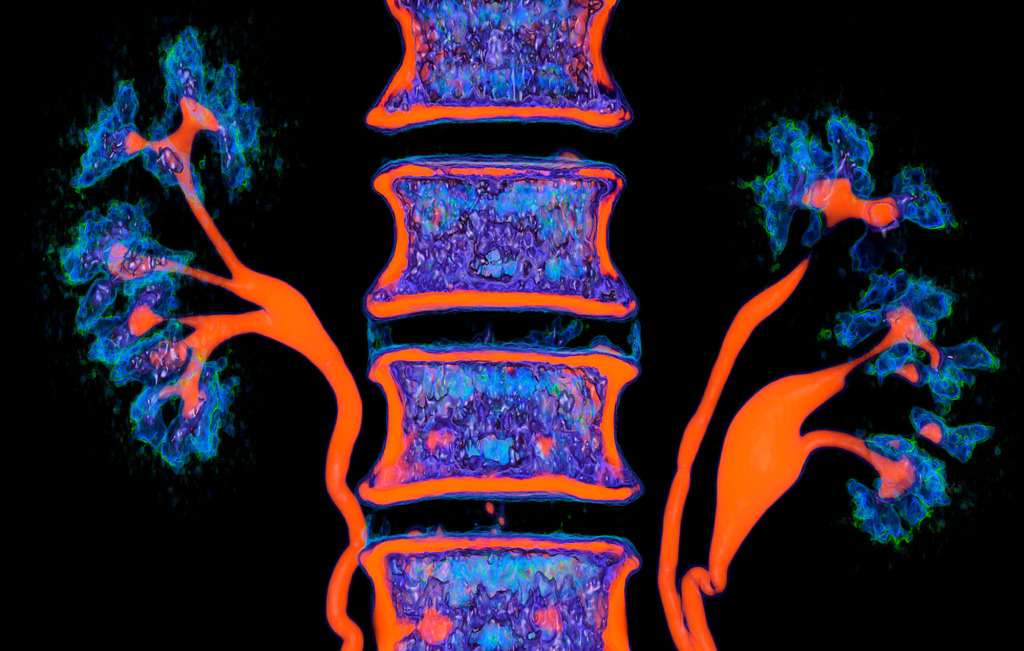

A multi-coloured, bright image is a way to shift the gaze and perceive things differently.

Also, I like to experiment with different photo filters and settings.

The colours choose themselves.

I simply create a table where the radiological density of the material can correspond to any colour.

After combining different shades, I only have to choose what I like the most.

No. Tissues with different densities are best suited to visualisation by CT imaging.

Lungs and heart, bones and muscles or organs injected with a contrast agent reveal the best structure and anatomy.